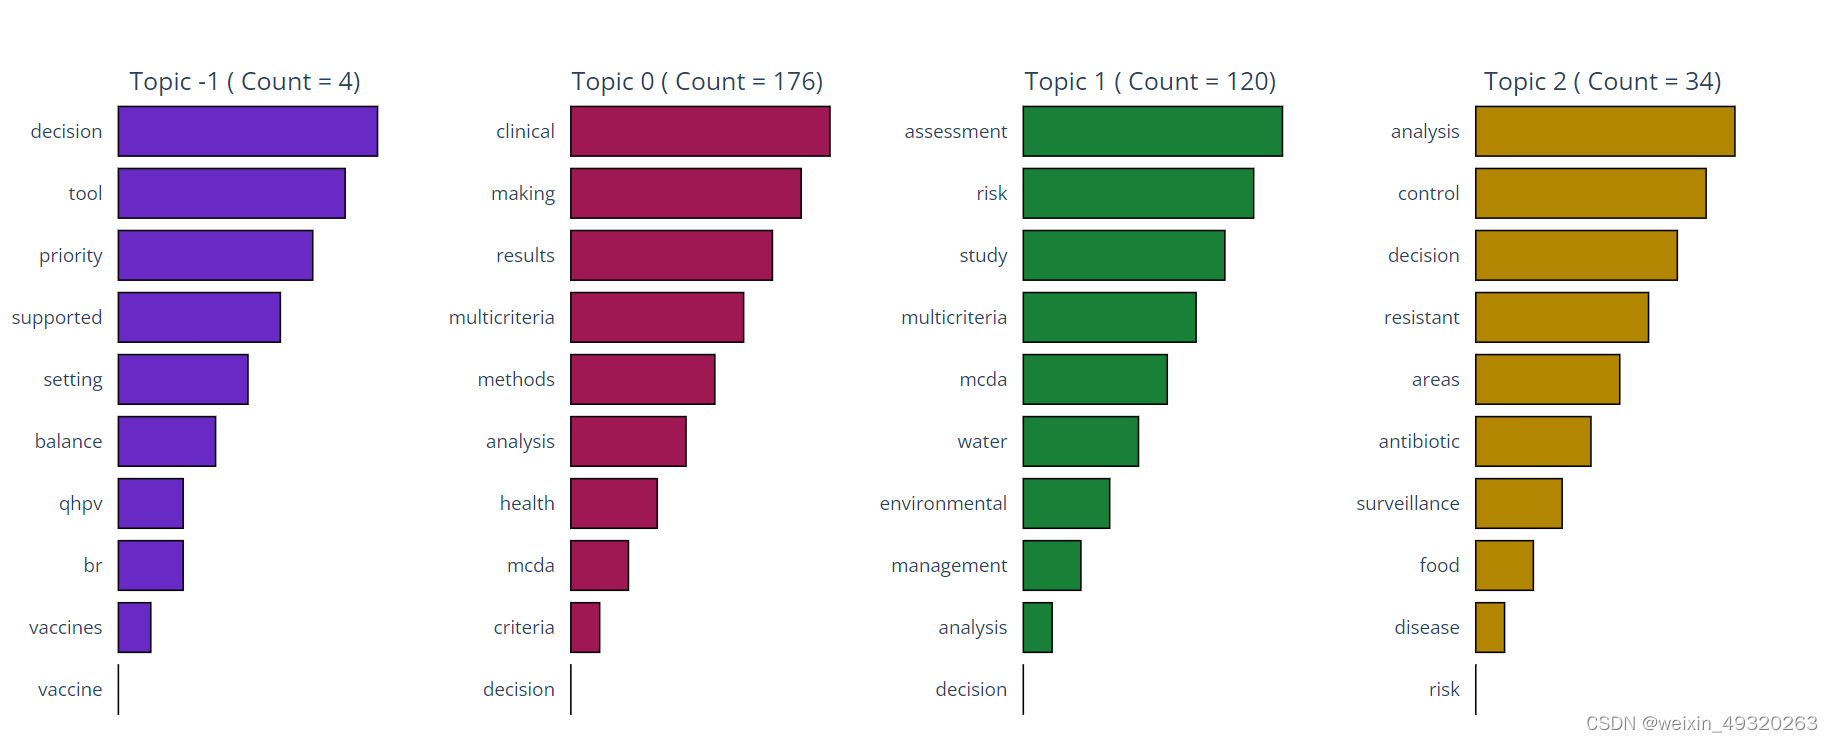

3.13 NLP:自然语言处理

# NLP

# Arguments: corpus_type = 'abs', 'title', 'kwa', or 'kwp';

# stop_words = A list of stopwords to clean the corpus. ['ar', 'bn', 'bg', 'cs', 'en', 'fi', 'fr', 'de', 'el', 'hi', 'he', 'hu', 'it', 'ja', 'ko', 'mr', 'fa', 'pl', 'pt-br', 'ro', 'ru', 'es', 'sv', 'sk', 'zh', 'th', 'uk'];

# 'ar' = Arabic; 'bn' = Bengali; 'bg' = Bulgarian; 'cs' = Czech; 'en' = English; 'fi' = Finnish; 'fr' = French; 'de' = German; 'el' = Greek; 'he' = Hebrew;…n;

# 'ja' = Japanese; 'ko' = Korean; 'mr' = Marathi; 'fa' = Persian; 'pl' = Polish; 'pt-br' = Potuguese-Brazilian; 'ro' = Romanian; 'ru' = Russian; 'es' = Spanish; 'sk' = Slovak; 'sv' = Swedish;

# 'zh' = Chinese; 'th' = Thai; 'uk' = Ukrainian

# rmv_custom_words = A list of custom stopwords to clean the corpus;

bibfile.create_embeddings(stop_words = ['en'], rmv_custom_words = [], corpus_type = 'abs')

emb = bibfile.embds

# NLP #-1 refers to all outliers and should typically be ignored.

# Arguments: stop_words = A list of stopwords to clean the corpus. ['ar', 'bn', 'bg', 'cs', 'en', 'fi', 'fr', 'de', 'el', 'hi', 'he', 'hu', 'it', 'ja', 'ko', 'mr', 'fa', 'pl', 'pt-br', 'ro', 'ru', 'es', 'sv', 'sk', 'zh', 'th', 'uk'];

# 'ar' = Arabic; 'bn' = Bengali; 'bg' = Bulgarian; 'cs' = Czech; 'en' = English; 'fi' = Finnish; 'fr' = French; 'de' = German; 'el' = Greek; 'he' = Hebrew;'hi' = Hindi; 'hu' = Hungarian; 'it' = Italian;

# 'ja' = Japanese; 'ko' = Korean; 'mr' = Marathi; 'fa' = Persian; 'pl' = Polish; 'pt-br' = Potuguese-Brazilian; 'ro' = Romanian; 'ru' = Russian; 'es' = Spanish; 'sk' = Slovak; 'sv' = Swedish;

# 'zh' = Chinese; 'th' = Thai; 'uk' = Ukrainian

# rmv_custom_words = A list of custom stopwords to clean the corpus;

# embeddings = True or False. If True then word embeddings are used to create the topics

bibfile.topics_creation(stop_words = ['en'], rmv_custom_words = [], embeddings = True)

# NLP

# Each document Topic

topics = bibfile.topics

# NLP

# Each document Probability to belong a Topic

probs = bibfile.probs

# NLP

# Arguments: view = 'notebook', 'browser' ('notebook' -> To plot in your prefered Notebook App. 'browser' -> To plot in your prefered browser window)

bibfile.graph_topics_distribution(view = 'notebook')

# NLP

# Arguments: view = 'notebook', 'browser' ('notebook' -> To plot in your prefered Notebook App. 'browser' -> To plot in your prefered browser window)

bibfile.graph_topics(view = 'notebook')